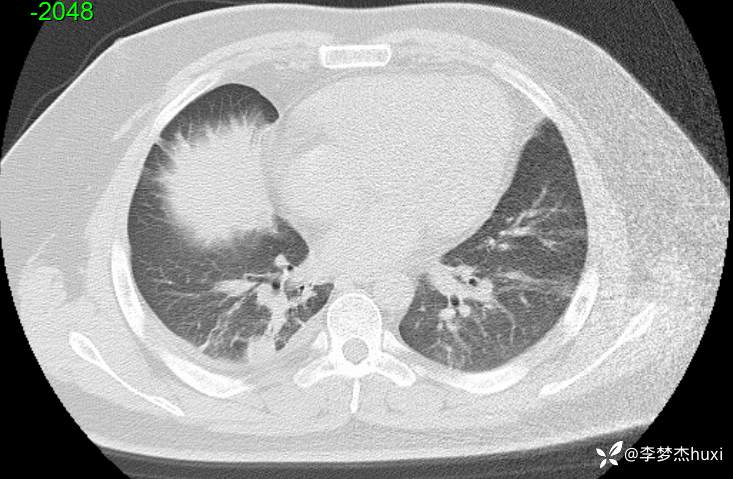

【现病史及既往史】: 1.患者青年 男,患者缘于2天前无诱因出现胸痛,为前胸痛,伴后背疼痛,咳嗽及深呼吸时明显,伴咳嗽,痰不易咳出,伴恶心、呕吐,伴发热,体温最高达37.7℃,无寒战,无咯血,院外未应用药物治疗,症状无明显好转,为求进一步治疗来院就诊,门诊查胸部CT提示:双肺炎症,较前进展,双肺纹理增重,右肺实性结节,建议随诊复查,双侧胸膜局部增厚,右侧胸腔少量积液。以“肺炎”收住院;。

【检查】: 4.辅助检查:心电图示:窦性心动过速,门诊查胸部CT提示:双肺炎症,较前进展,双肺纹理增重,右肺实性结节,建议随诊复查,双侧胸膜局部增厚,右侧胸腔少量积液。